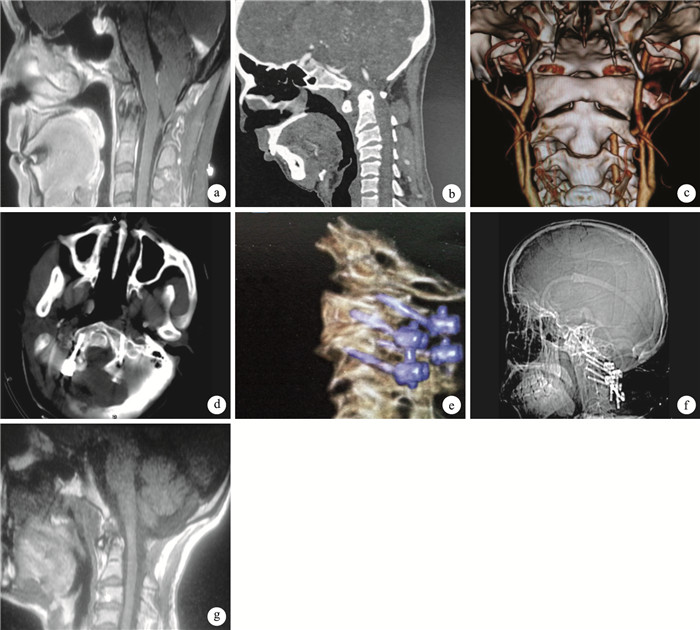

術后1例術后第3天拔除引流管后出現腦脊液切口漏,腰大池引流7 d后切口愈合良好,腦脊液漏消失。其余患者切口均Ⅰ期愈合,無手術早期并發癥發生。患者均獲隨訪,隨訪時間6個月~2年,平均18.4個月。患者神經功能障礙均有不同程度改善,術后6個月時日本骨科協會(JOA)評分為(16.12±1.11)分,較術前的(11.76±2.01)分明顯提高,比較差異有統計學意義(t=13.596,P=0.000)。X線片復查示,術后6個月內植骨均達融合。MRI復查示,全部患者寰樞關節復位良好,脊髓及延髓受壓改善;10例合并脊髓空洞者3例空洞消失,6例空洞變小,1例無明顯變化。見圖 1。